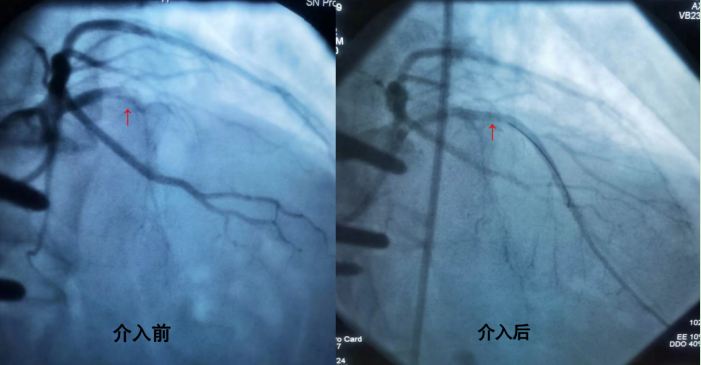

19:02分患者到达导管室,经股动脉进行穿刺、消毒、铺巾,整个动作一气呵成;患者既往因脊柱侧弯行胸椎内固定术,导致心脏位置形态异常,加之紧张桡动脉痉挛,这无疑给心脏介入团队增加难度,但大家没有放弃,造影结果显示:前降支近段闭塞,19:26分导丝通过闭塞血管,术中出现了慢血流、再灌注心律失常、低血压、心衰等并发症,经过积极处理,在罪犯血管前降支近段顺利植入支架,血流逐渐恢复正常,生命体征平稳,手术获得成功。随后将患者转入CCU继续诊治。